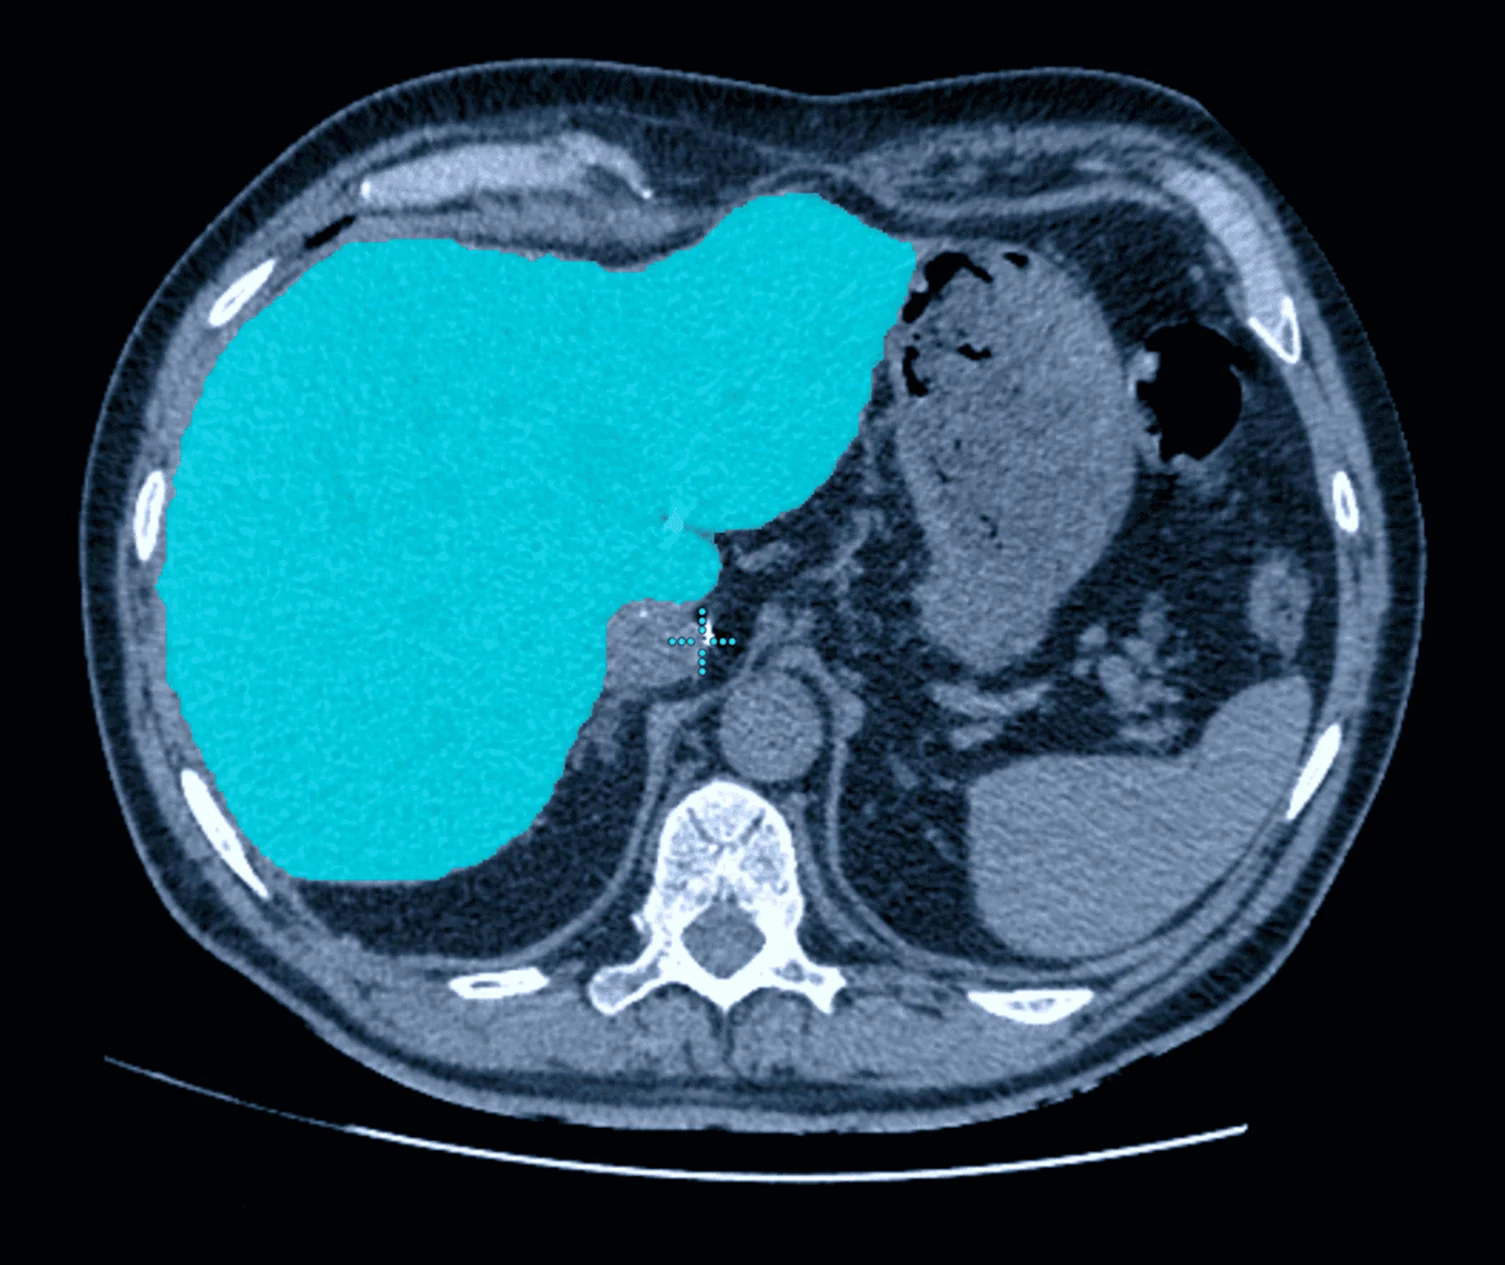

• Accurate Organ Segmentation

Precise segmentation is essential for training medical AI models that require detailed anatomical or pathology-level understanding. High-accuracy masks enable models to measure volumes, isolate target regions, track disease progression, and differentiate tissue types with clinical reliability. Inaccurate segmentation introduces noise into the training dataset, resulting in unstable models, poor generalization, and reduced diagnostic value. High-fidelity segmentation ensures your AI performs consistently, safely, and at a standard suitable for clinical applications.